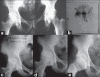

Materials and methods: The article comprises of the retrospective study of 31 patients of osteonecrosis of femoral head in stage II and III treated with core decompression and vascular pedicle grafting by using part of iliac crest with deep circumflex iliac vessels from January 1990 to December 2005. The young patients with a mean age 32 years (18-52 years) with a minimum follow-up of five years were included for analysis. Sixteen patients had osteonecrosis following alcohol abuse, 12 patients following corticosteroid consumption, 3 patients had idiopathic osteonecrosis. Nine patients were stage IIB, and 22 patients were stage IIIC according to ARCO's system. The core decompression and vascular pedicle grafting was performed by anterior approach by using part of iliac crest with deep circumflex iliac vessels.

Results: Digital subtraction arteriography performed in 9 patients at the end of 12 weeks showed the patency of deep circumflex artery in all cases, and bone scan performed in 6 other patients showed high uptake in the grafted area of the femoral head proving the efficacy of the operative procedure. Out of 31 patients, only one patient progressed to collapse and total joint replacement was advised. At the final follow up period of 5-8 years, Harris Hip Score improved mean +/- SD of 28.2 +/- 6.4 (p < 0.05). Forty-eight percent of patients had an improvement in Harris Hip Score of more that 28 points.